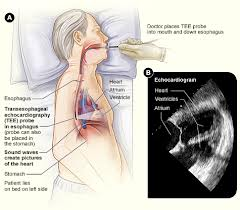

اکوکاردیوگرافی از طریق مری: برای تشخیص دقیق مشکلات قلبی بعضی مواقع اکوکاردیوگرافی از طریق مری انجام میشود که با توجه به مجاورت مری و قلب تصاویر شفافی از قلب بدست میآید که بخصوص در تشخیص اختلالات آئورت ، اختلال عملکرد دریچههای مصنوعی ، تودههای دهلیز چپ و … مفید است.

امکان تصویربرداری دو بعدی و داپلر قلب از طریق مری با بلع یک گاستروسکوپ دارای کریستال فراصوت در نوک آن توسط بیمار امکانپذیر میشود.